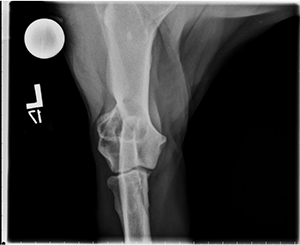

Radiographs of the left elbow show the following:

Cranial-caudal view: